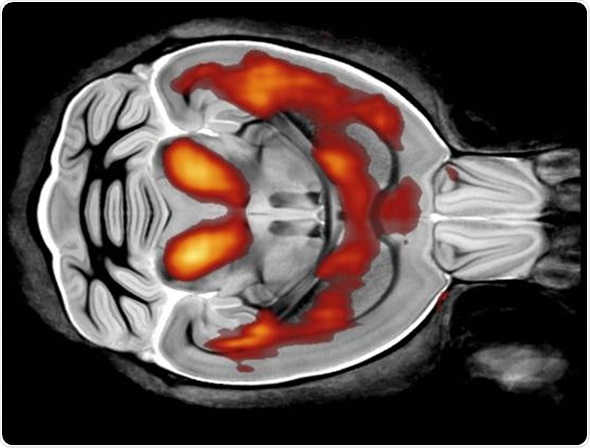

In terms of research projects, what I'm really interested in is a technique called diffusion MRI. The beauty of using this technique is that it can give you information about the microstructure of tissue.

On a clinical scanner, the MRI voxel is probably about a millimeter in length, whereas the kind of spatial information that we want is a thousand times smaller than that, it’s about a micron in size.

So, how do we get spatial information on the scale of microns when the actual voxel is about a millimeter long? We use diffusion MRI, because we can look at the way water diffuses within the cell.

If you have an axon for example, which is a long, thin tube, water is relatively free to diffuse along it, but it is restricted when it comes to going across the axon.

By looking at different diffusion times, we can infer the size of the axon. In particular, axon diameter estimates are important in the diagnosis of many neurodegenerative diseases.